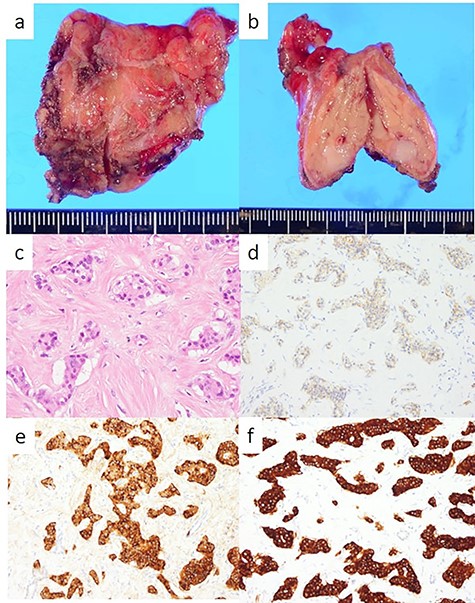

The head tumor was a yellow 38 × 20 × 14 mm solid tumor with capsule, protruding into the duodenum (Fig. 3). Histopathology revealed abundant nests of large clear cells with nested architecture and prominent vasculature (Fig. 3). Immunohistochemistry staining showed positive immunoreactivity for PAX8, suggesting metastasis of RCC (Fig. 3). By contrast, the tail tumor was a white 6 × 6 mm solid tumor with defined cell borders. Histopathology revealed atypical cells with hyperchromatic nuclei in the nests (Fig. 4). Immunohistochemistry showed the following pattern: CD56 (+), chromogranin A (+), synaptophysin (+), Ki67 0.8% (4/489) (Fig. 4). Thus, the tail tumor was diagnosed as a pancreatic neuroendocrine tumor, G1.

Resected specimen and pathological findings of the pancreatic head tumor; (a, b) a yellow 38-mm solid tumor in the pancreatic head protruding into the duodenum; (c) abundant nests of large clear cells (hematoxylin and eosin ×400); (d) immunohistological positivity for PAX8 (PAX stain ×200).